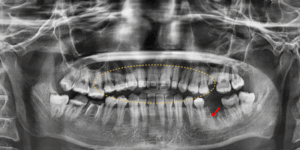

교정을 먼저 진행하면서

왼쪽아래의 뿌리만 남아있던 어금니를

가장 먼저 발치해주었습니다.

이후 오른쪽 위 사랑니와

심하게 손상되어 뿌리만 남아있던

왼쪽 위,오른쪽 아래 어금니를 발치해주었습니다.

이후 나머지 매복된 사랑니를 모두 발치하였고

교정을 통해서 쓰러져있던 치아들이

바로 세워졌습니다.